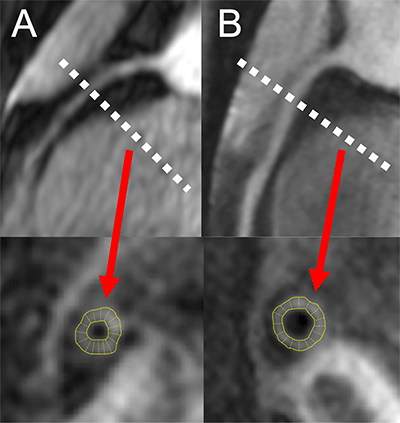

MR angiograms (top row) of the right coronary arteries in two persons living with HIV (PLWH) show location of cross-section (dotted lines) of coronary vessel wall image (bottom row) and the corresponding automatic wall thickness measurement. (A) Image from 50-year-old male PLWH with increased coronary vessel wall thickness of 1.5 mm and grade 1 diastolic dysfunction. (B) Image from 52-year-old male PLWH with coronary vessel wall thickness of 1.2 mm and normal diastolic function.

The results showed increased coronary vessel wall thickness in the HIV group, compared to controls. The increased coronary artery vessel wall thickness was independently associated with elevated left ventricular mass index and impaired diastolic function.